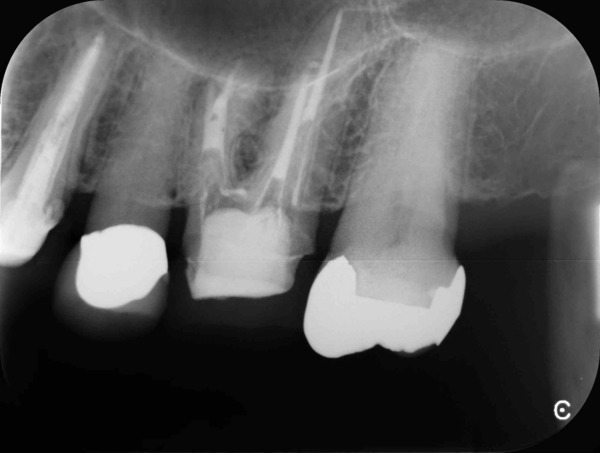

術前のレントゲン写真とお口の中の状態です。左上の前から6番目の歯(#26)です。

3本ある内の手前(近心)の根の中には治療用の器具が折れて残っていました。折れた器具が根管の中にあるだけでは問題になることは少ないですが、その先に感染がある場合は取り除いて治療をすることが望ましいです。

歯根の中の画像です。折れて残っている器具が確認できます。

超音波の器具を用いて取り除いていきます。今回は無事に取り除くことができました。

根の中を詰めた直後のレントゲン写真です。